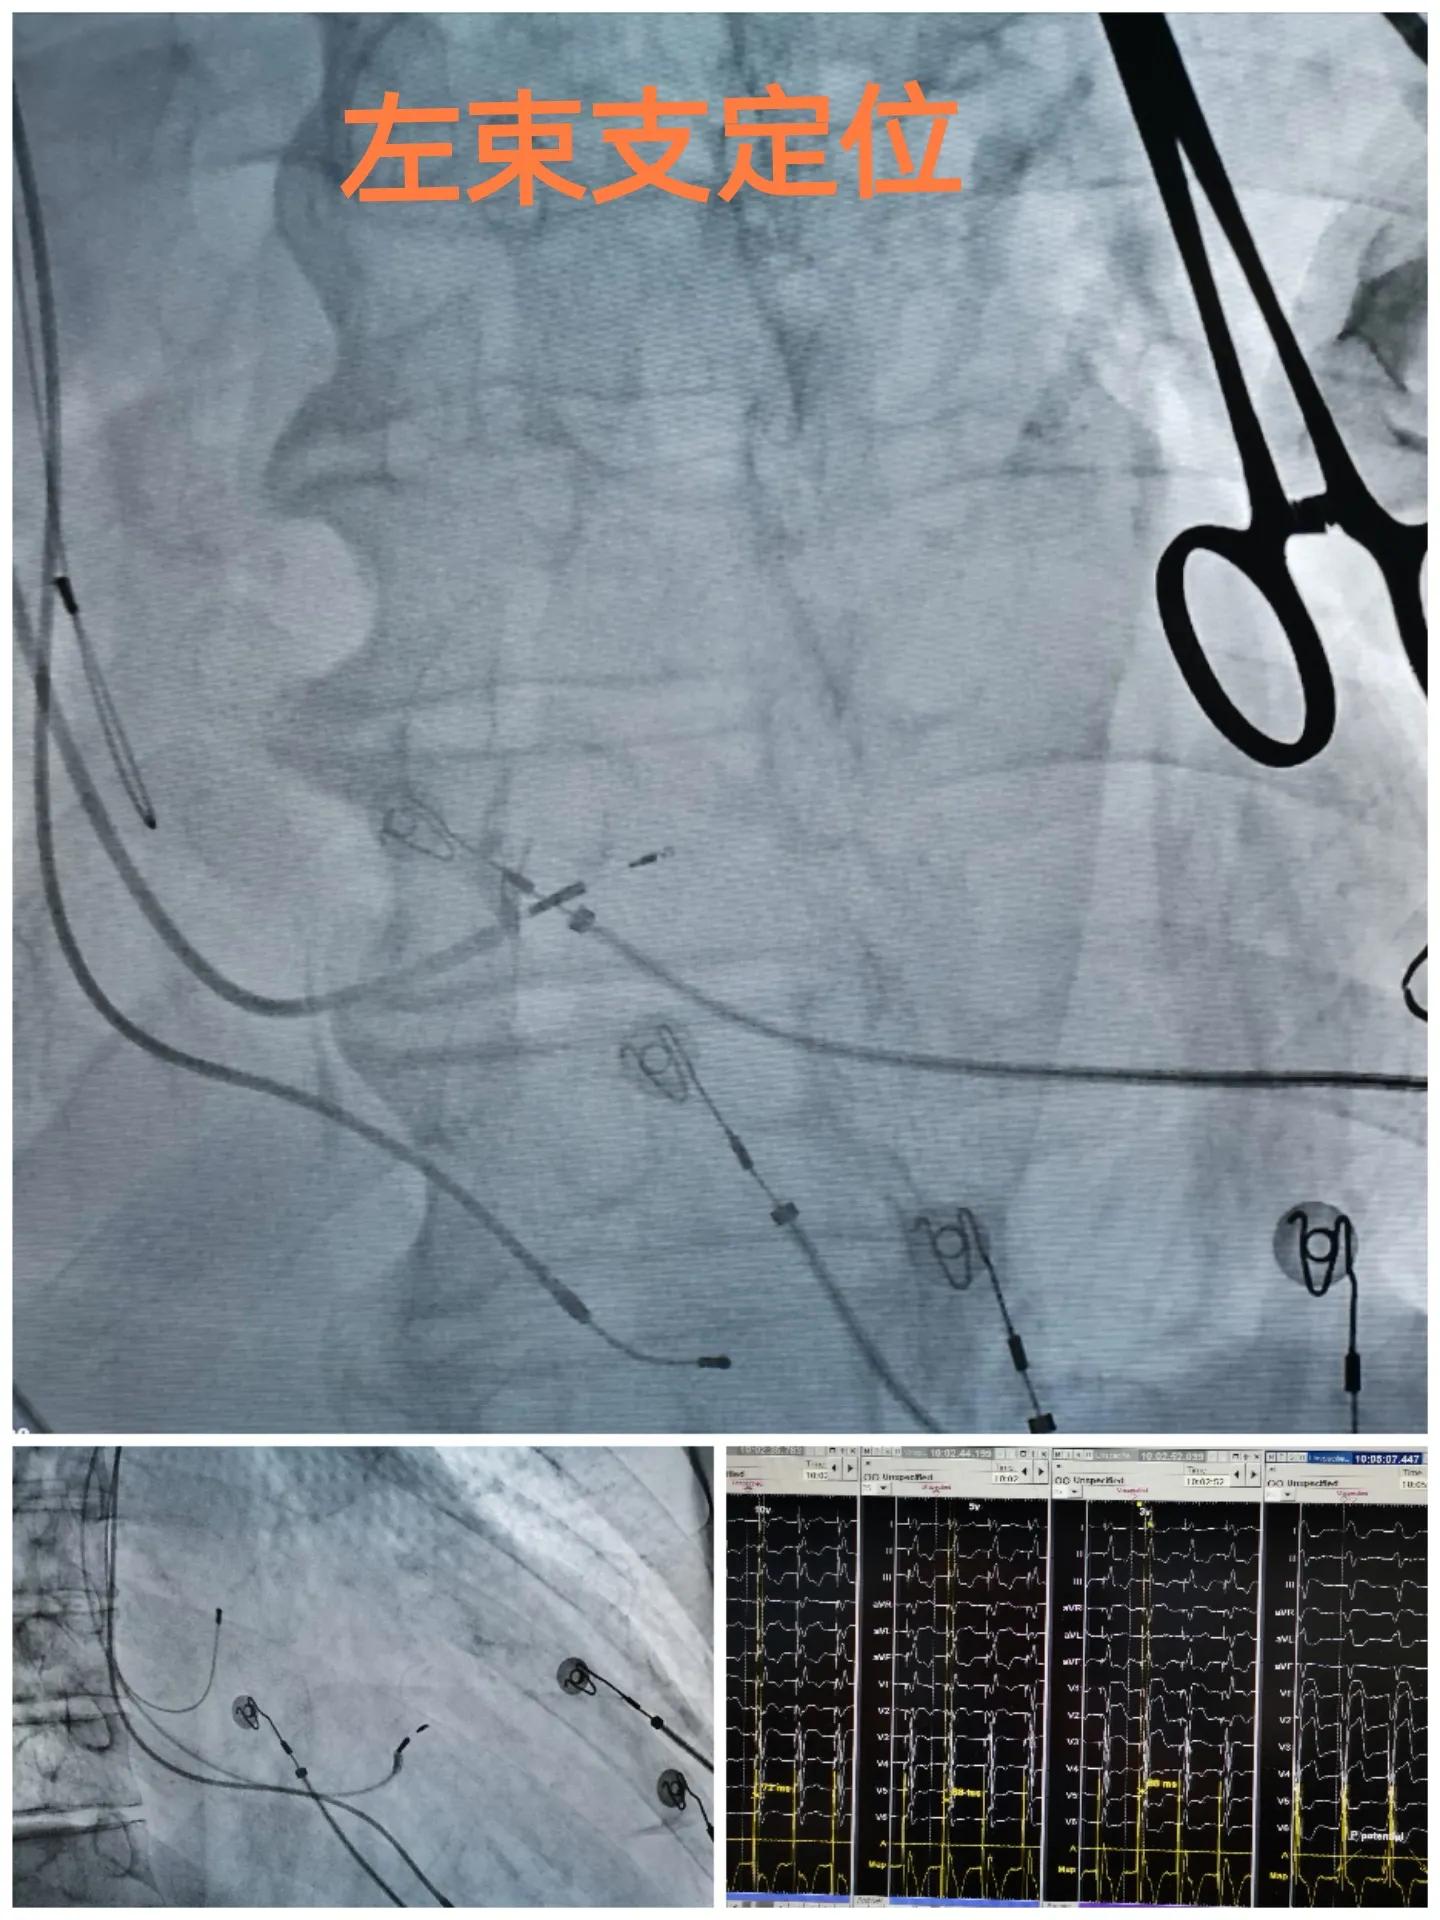

我们尝试左束支起搏,术中顺利,依次找到His,定位到左束支。

纯左束支起搏的QRS宽度为144ms,通过调整AV间期后,QRS宽度进一步减少至104ms,窄的令人感动!